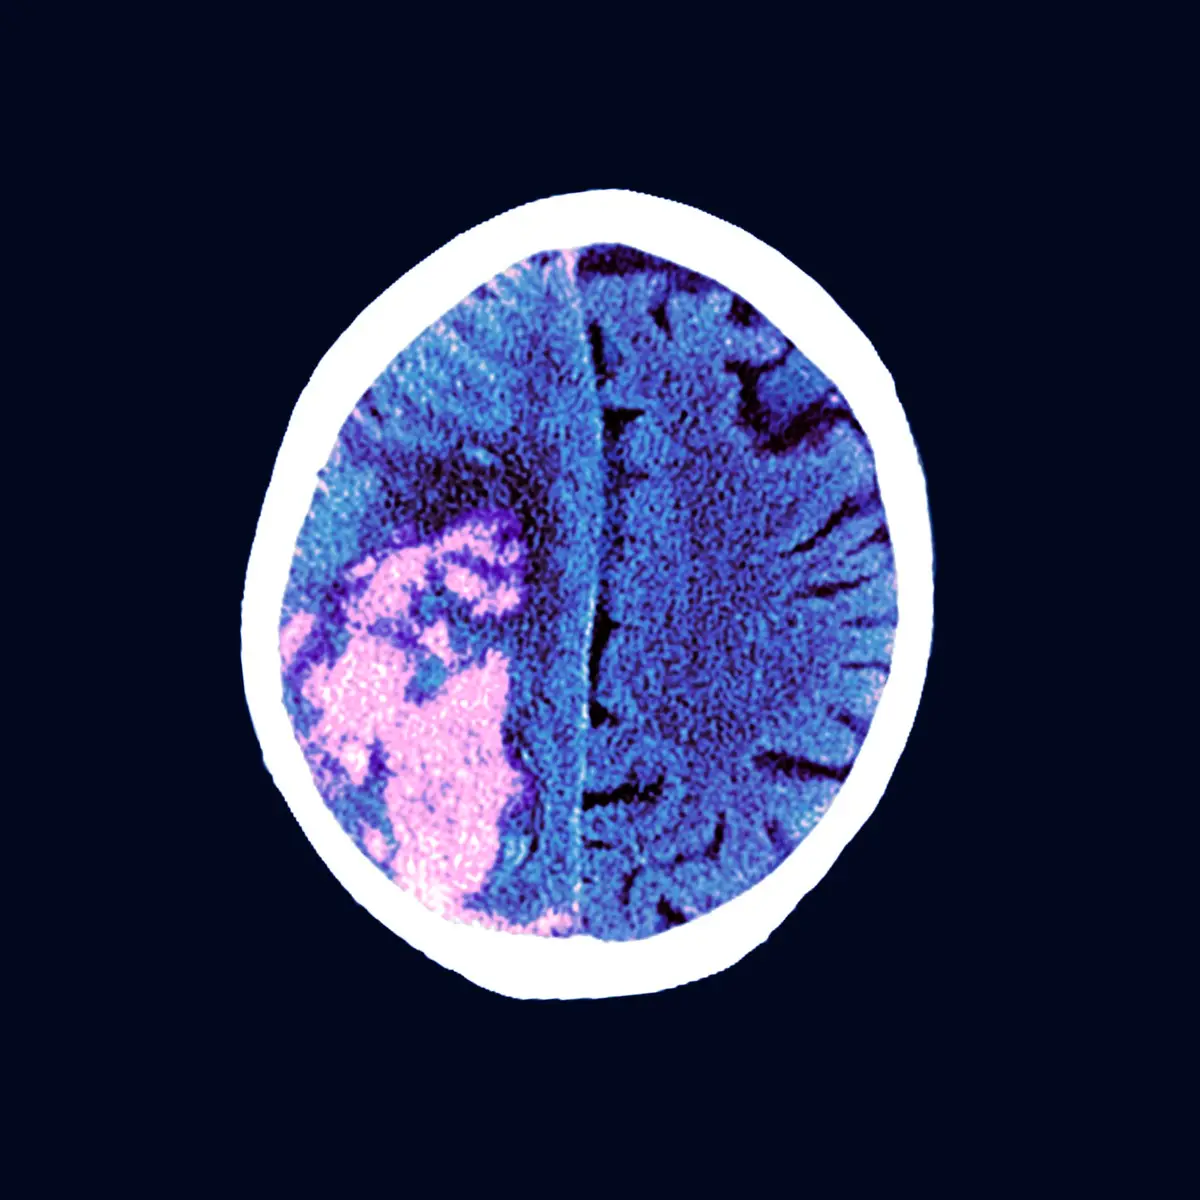

Silent strokes can only be identified through a brain CT scan or an MRI. The images will show white spots or lesions where the brain cells have stopped functioning.